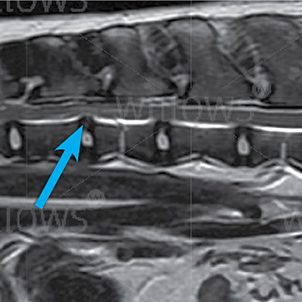

Fig 1: MRI scan showing a traumatic disc extrusion in the neck (arrow)

X-rays of the spine may show that the space where an affected disc lies looks narrower than normal, suggesting that some of the disc material has moved out of position. More advanced investigations are necessary to see if a disc has actually ruptured and to assess if it is pressing on the spinal cord. An MRI scan provides the best method of investigating this condition. MRI uses high powered magnets and a computer to generate images of the spine and provides information not only on the health and position of the discs in the spine but also on the nature of any injury to the spinal cord. This makes diagnosis more accurate and assists greatly in deciding the best course of treatment for the individual patient.